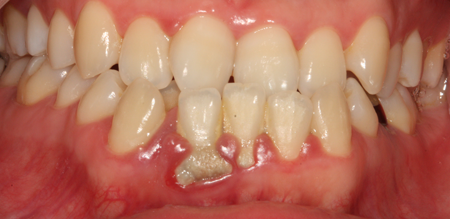

치주치료

청담네오플란트는 치주치료를 통하여 치아를 살릴 수 있는 기회를 놓치지 않습니다.

치주염(잇몸병)은 치아에 붙어있는 치석 및 세균 등에 의한 염증반응으로 잇몸뼈가 상실되는 질환을 말합니다.

초기에는 잇몸이 붓거나 잇몸에서 피가 나는 증상이 나타나며 계속 방치하면 치아를 발치해야 할 수도 있습니다.

치주치료는 이러한 치석 및 세균 등을 제거하여 잇몸뼈를 안정된 상태로 유지하는 시술을 말하며, 청담네오플란트에서는 치의학박사 / 전문의가 직접 시술하고 있습니다.

치주염 (말기)

잇몸이 항상 부어 있으며, 이가

흔들리는 정도가 점점 심해짐.

치주치료가 필요하며, 정도에 따라 치아를 발치하여야 할 수 있음.

치주치료 전후사진